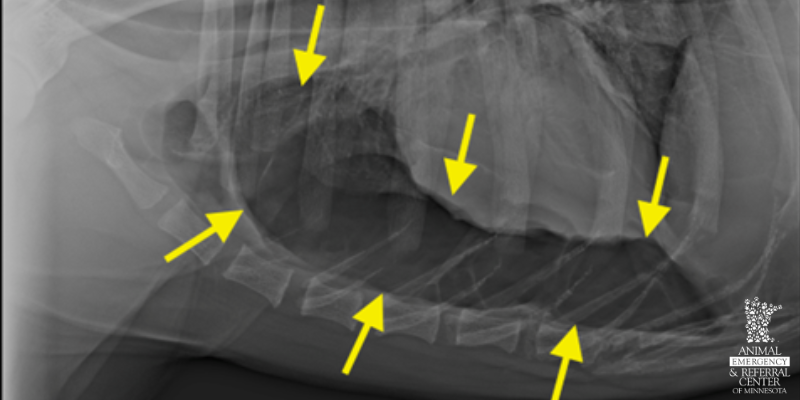

Chest x-ray in a young adult dog with sudden breathing difficulty. There is free gas in the pleural space (space around the lungs), highlighted by arrows. This results in compression of the lungs and pushes the heart up on the x-ray. Sometimes this can be treated medically by removing the free gas, but continuous or severe air leaks require surgery to remove the leaking portion of the lung.